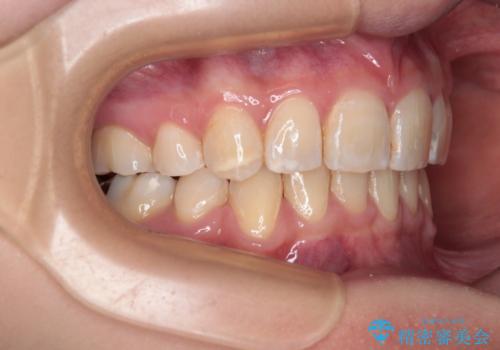

- 前方に飛び出した前歯と、下顎の八重歯を気にして来院された患者様です。

口元の突出感を改善するため、上下左右の第一小臼歯4本を抜歯し、ワイヤー装置にて矯正治療を行うこととしました。

抜歯矯正により、口元の印象だけでなく、横顔の印象も大きく改善されました。